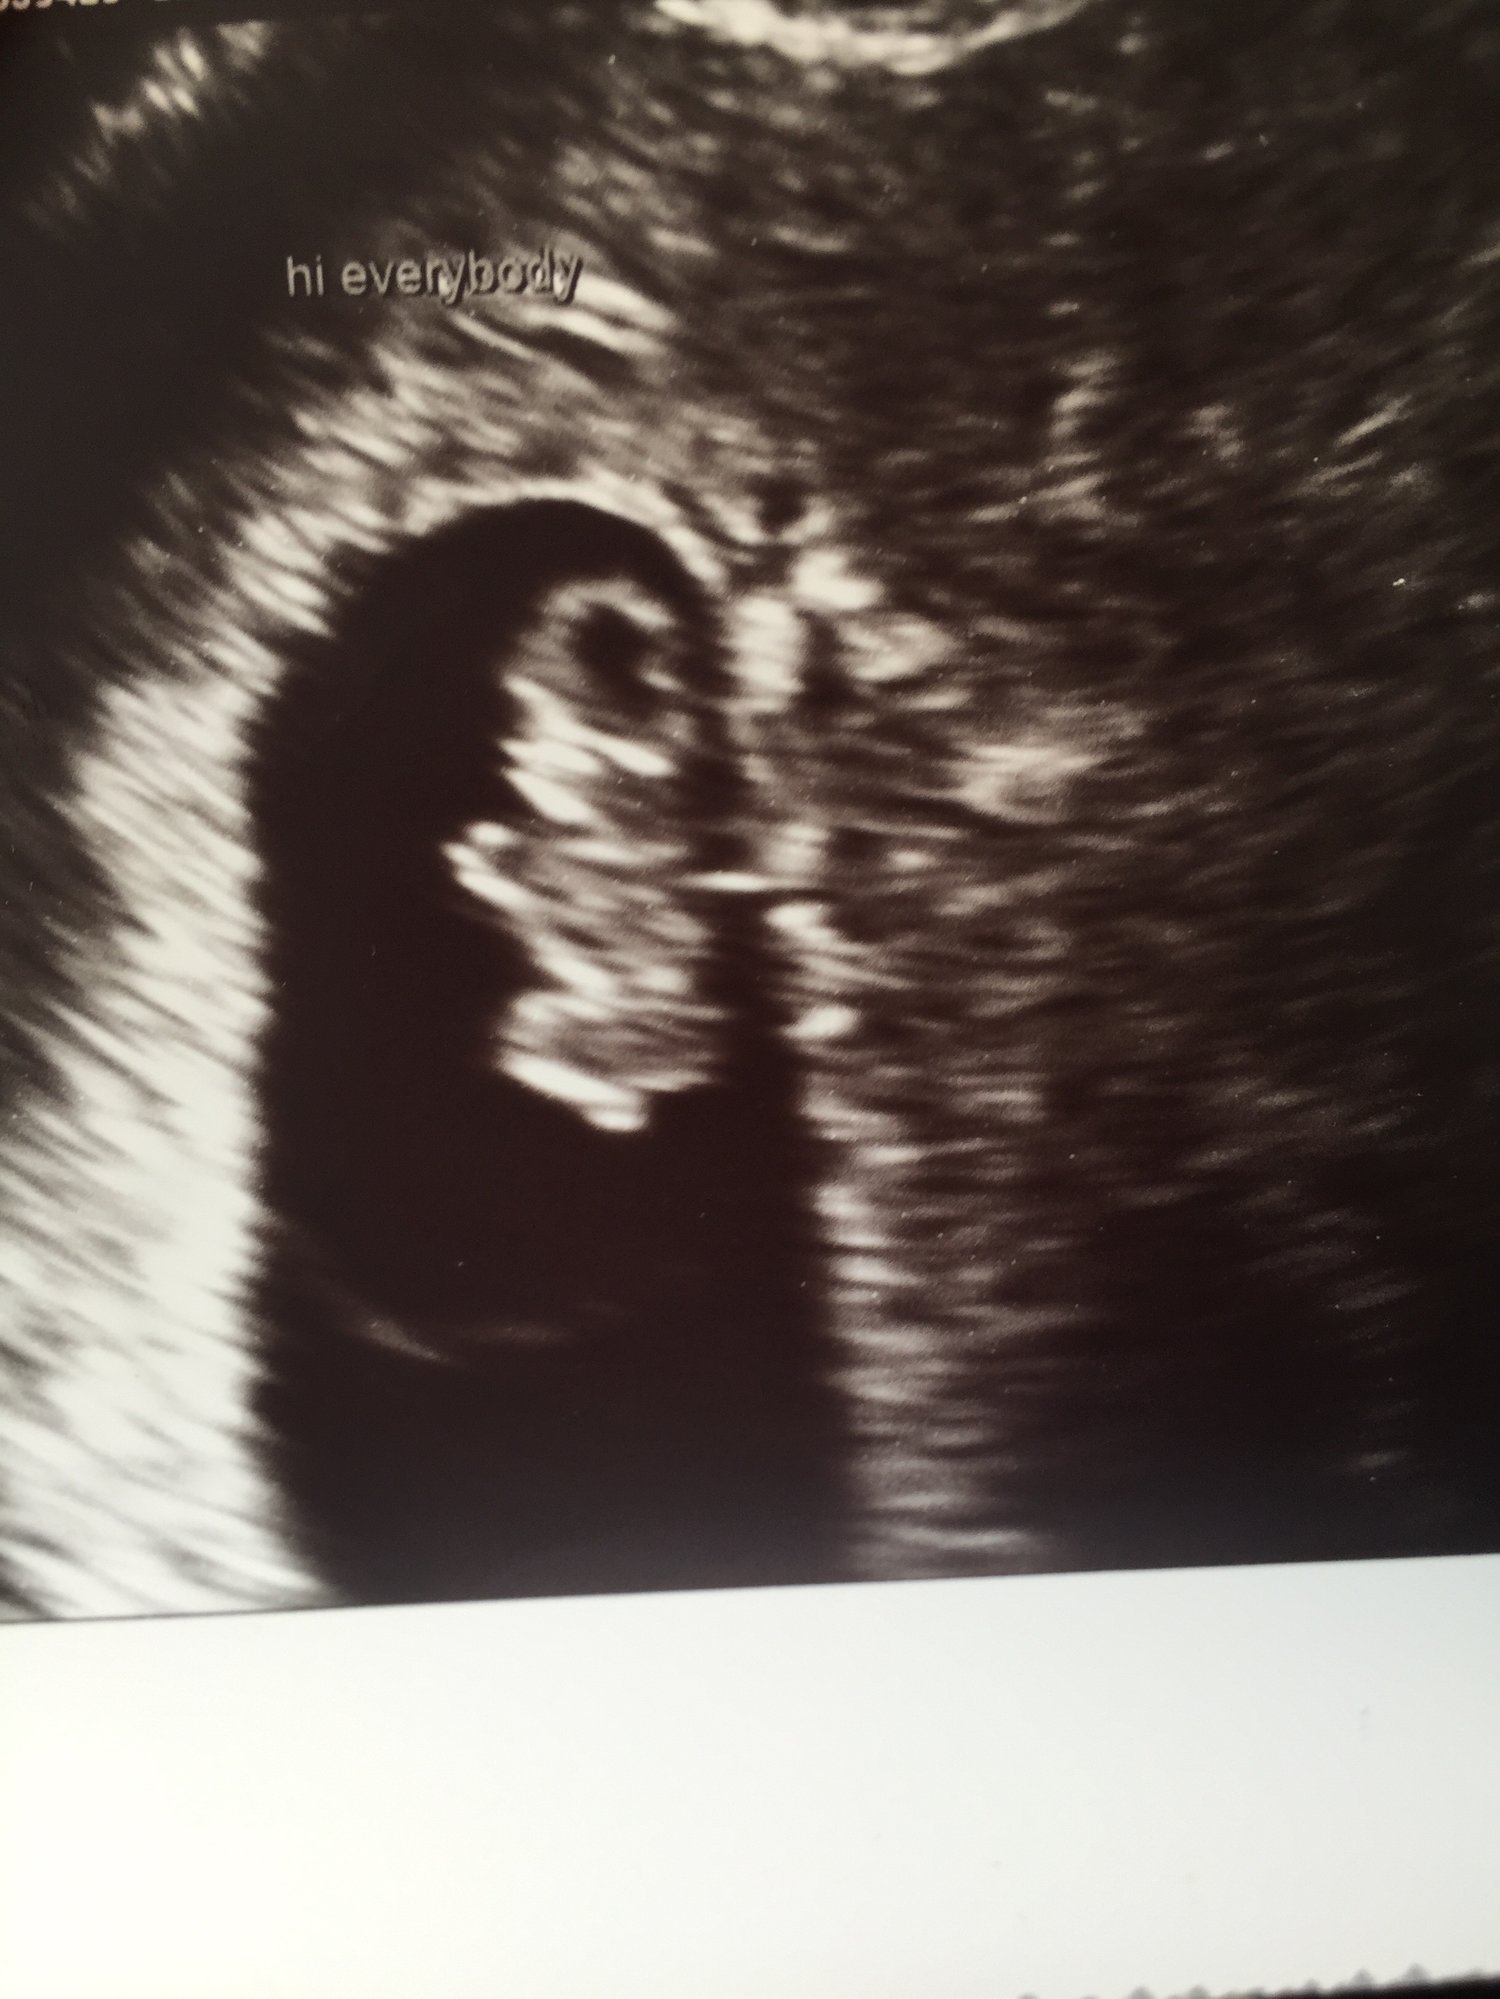

I got to see my two little ones and hear their heartbeats again this week at 7w4d. They are pretty clearly di/di. I "graduated" from the REs office and cried in the elevator leaving, it was really overwhelming. Sorry to keep posting all my ultrasound photos but staring at them is the only thing that keeps me from losing my mind with all the nausea and vomiting. And we haven't told anyone else so I have to keep telling you all!